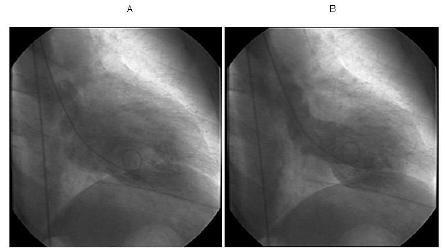

We report a unique case of a 60-year-old Hispanic woman with myasthenia gravis who developed takotsubo cardiomyopathy and concomitant myasthenic crisis that appear to have been triggered by a stressful life event. On admission, she presented with severe mid-sternal chest pain and shortness of breath shortly after a personally significant stressful life event. A pertinent neurological examination showed bilateral facial weakness and right ptosis. The left ventriculogram showed apical ballooning with hyperdynamic proximal segments with sparing of the apex. Her troponin I level was elevated, while cardiac catheterization revealed no significant coronary artery disease. The findings were consistent with takotsubo cardiomyopathy. Shortly after cardiac catheterization, she developed bilateral ophthalmoparesis and significant bulbar and respiratory muscle weakness. Forced vital capacity values were persistently less than 1 L. The patient developed respiratory failure and required endotracheal intubation. After plasmapheresis and corticosteroid treatment, her clinical course improved with successful extubation. A normal left ventricle chamber size and a normal ejection fraction were noted by an echocardiogram repeated 10 months later.

我们报告了一例独特的病例,一名60岁的西班牙裔重症肌无力女性患者,并发应激性心肌病和重症肌无力危象,似乎是由一次重大生活应激事件引发的。入院时,在经历一次对个人意义重大的生活应激事件后不久,她出现了严重的胸骨后胸痛和呼吸急促。相关神经系统检查显示双侧面部无力和右侧上睑下垂。左心室造影显示心尖部膨出,近端节段动力增强,心尖部未受累。她的肌钙蛋白I水平升高,而心脏导管检查显示无明显冠状动脉疾病。这些发现符合应激性心肌病。心脏导管检查后不久,她出现双侧眼球运动障碍以及明显的延髓和呼吸肌无力。用力肺活量值持续低于1升。患者出现呼吸衰竭,需要气管插管。经过血浆置换和皮质类固醇治疗,她的临床病程有所改善,成功脱机。10个月后复查超声心动图显示左心室腔大小正常,射血分数正常。